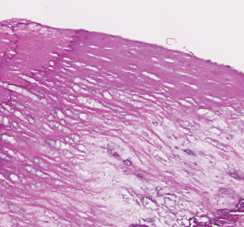

Coronary artery disease (CAD) is a cardiovascular condition with high morbidity and mortality. Intravascular optical coherence tomography (IVOCT) has been considered as an optimal imagining system for the diagnosis and treatment of CAD. Constrained by Nyquist theorem, dense sampling in IVOCT attains high resolving power to delineate cellular structures/ features. There is a trade-off between high spatial resolution and fast scanning rate for coronary imaging. In this paper, we propose a viable spectral-spatial acquisition method that down-scales the sampling process in both spectral and spatial domain while maintaining high quality in image reconstruction. The down-scaling schedule boosts data acquisition speed without any hardware modifications. Additionally, we propose a unified multi-scale reconstruction framework, namely Multiscale- Spectral-Spatial-Magnification Network (MSSMN), to resolve highly down-scaled (compressed) OCT images with flexible magnification factors. We incorporate the proposed methods into Spectral Domain OCT (SD-OCT) imaging of human coronary samples with clinical features such as stent and calcified lesions. Our experimental results demonstrate that spectral-spatial downscaled data can be better reconstructed than data that is downscaled solely in either spectral or spatial domain. Moreover, we observe better reconstruction performance using MSSMN than using existing reconstruction methods. Our acquisition method and multi-scale reconstruction framework, in combination, may allow faster SD-OCT inspection with high resolution during coronary intervention.